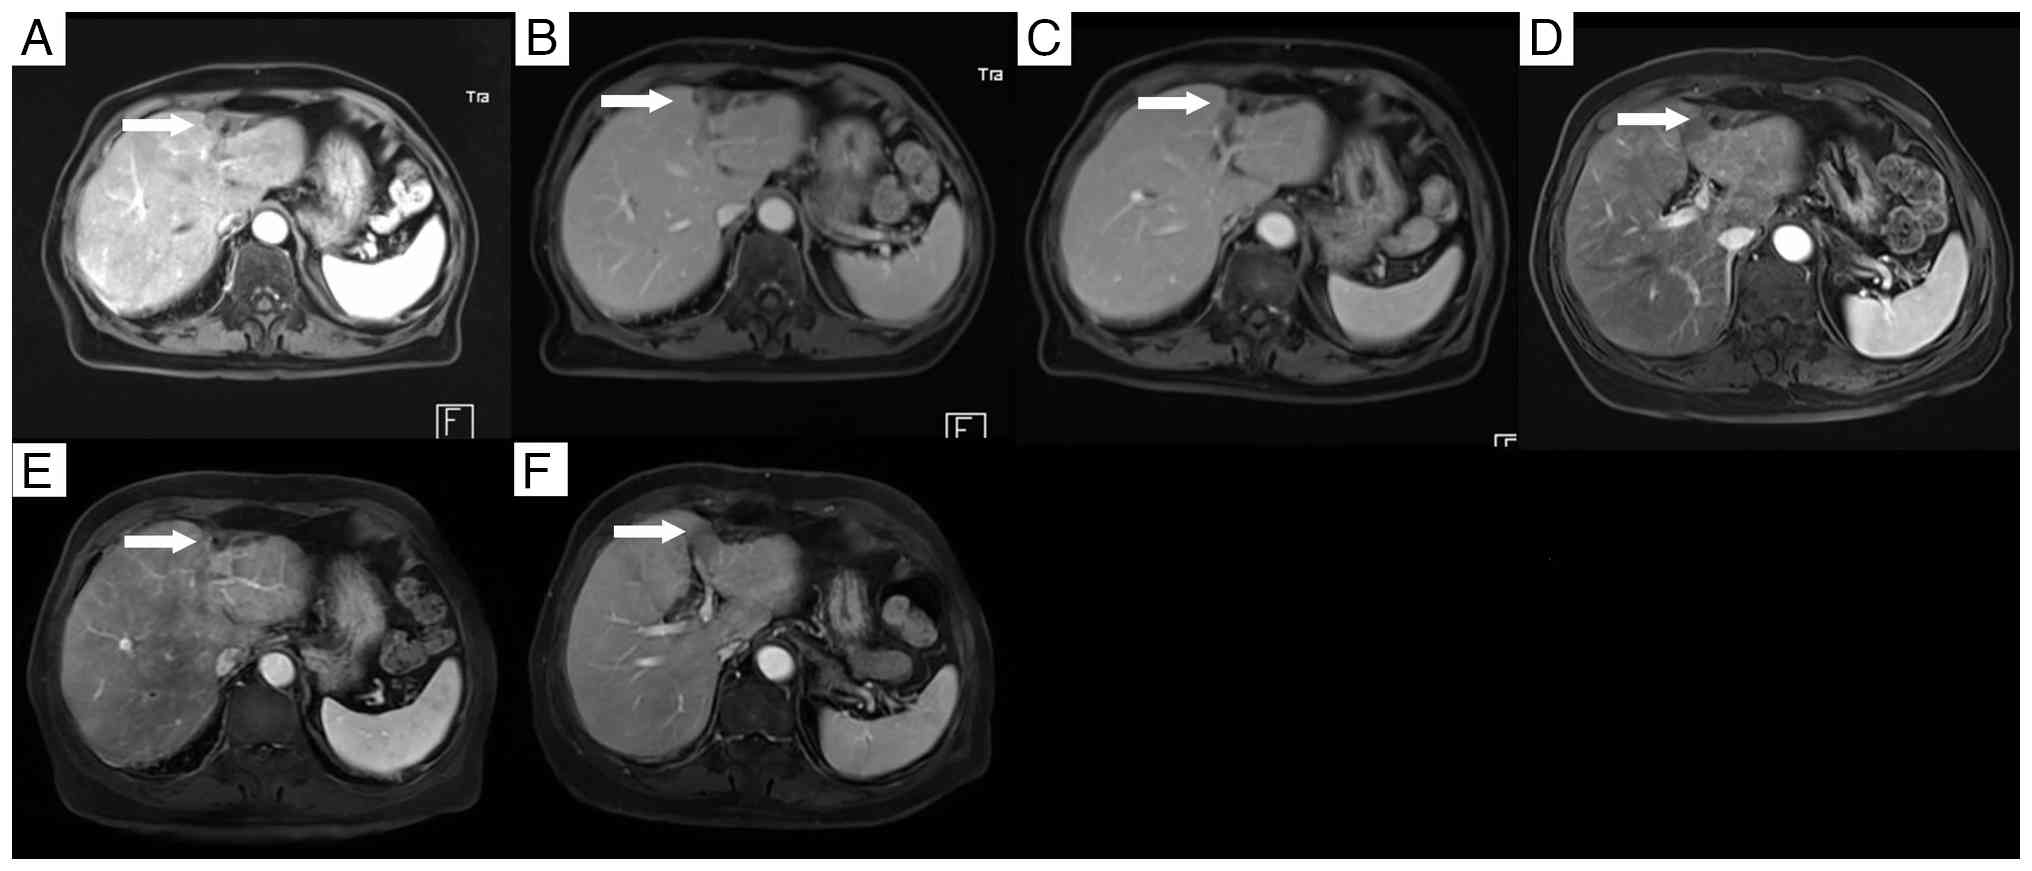

Follow-up by enhanced magnetic

resonance imaging. (A) The lesion measured 30×19 mm at 6 years

post-HIFU. At (B) 7, (C) 8, (D) 9, (E) 10 and (F) 11 years

post-high-intensity focused ultrasound, the left hepatic lobe shows

stable residual scar tissue without signs of recurrence.

Figure 10.

Follow-up by enhanced magnetic resonance imaging. (A) The lesion measured 30×19 mm at 6 years post-HIFU. At (B) 7, (C) 8, (D) 9, (E) 10 and (F) 11 years post-high-intensity focused ultrasound, the left hepatic lobe shows stable residual scar tissue without signs of recurrence.

Tumor marker levels, including carcinoembryonic antigen (CEA), α-fetoprotein (AFP), carbohydrate antigen (CA)12-5, CA15-3, and CA19-9, were monitored every 1–3 months from June 2013 to February 2014, and every 6–12 months thereafter until July 2015. An analysis of the timeline of changes in the patient's CEA levels, alongside the diagnosis and treatment of rectal cancer liver metastases, revealed that the main lesion was located in the left lobe of the liver. Before HIFU treatment for the left liver lesion, CEA levels remained elevated above the normal range. However, following HIFU treatment, CEA levels returned to a normal level (Fig. 8). AFP, CA12-5, CA15-3 and CA19-9 levels remained within the normal range throughout the disease course. Contrast-enhanced CT scans over the 2 years following HIFU therapy showed no evidence of tumor recurrence (Fig. 9). Beginning in the sixth year after surgery, annual contrast-enhanced MRI examinations were performed, facilitated by upgrades in the hospital's imaging equipment. These MRI studies confirmed the absence of tumor recurrence in the right hepatic lobe. In the left hepatic lobe, only residual scar tissue was observed, with no signs of tumor recurrence (Fig. 10).